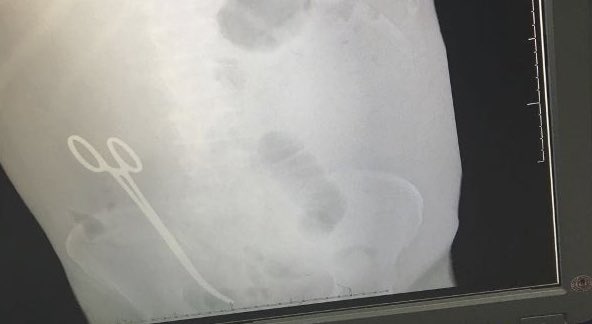

افتراضي طبيب ينسى مقص في بطن مريض بعد عملية جراحية في مستشفى بحائل ( صورة )

هذه نتيجة الأخطاء الطبية في مستشفياتنا وهذه فرصة لوزير الصحة الجديد توفيق الربيعة لضرب بيد من حديد لهؤلاء الأطباء الفاشلين الذين استهانوا بصحة المرضى